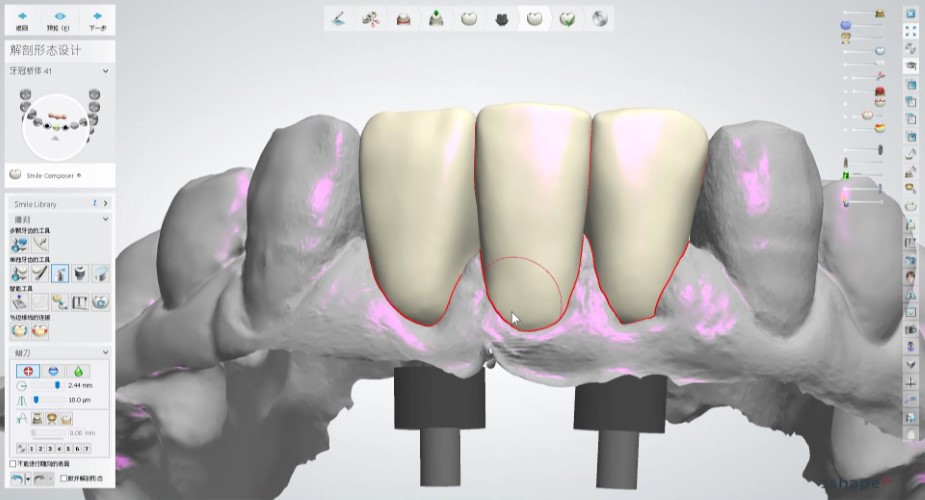

在術前規劃會使用數位化設計軟體,利用數位印模和數位排牙,精準地設計未來的牙齒排列和咬合狀態,更能真實模擬未來正式假牙效果,讓假牙設計既貼合個人需求,也更接近理想的美觀與舒適。

![]() |

數位排牙可以預先模擬出手術後的效果,方便跟患者溝通,有任何想調整的地方也可以事先討論,讓整個過程更安心、更有把握。